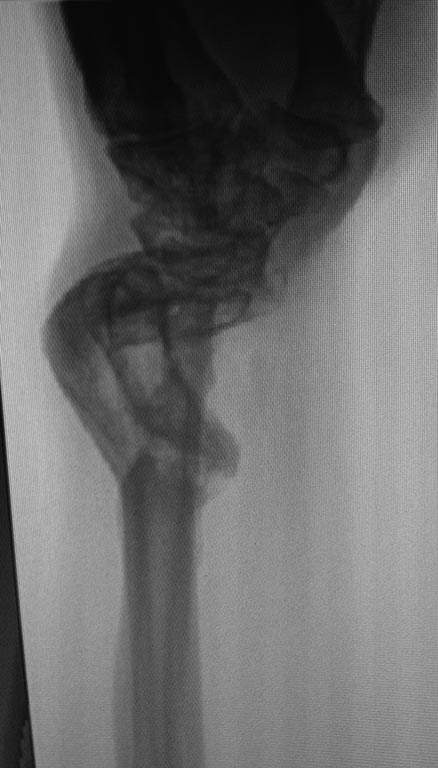

Предлагаю обсудить возможную тактику лечения пациента с деформацией

костей предплечья.

Пациент получил огнестрельное ранение левого предплечья с переломом

обеих костей в нижней трети в августе 2014г. Первоначально лечился в

аппарате Илизарова. Со слов пациента, в связи с развитием ИО в область

проведения спиц аппарат демонтирован, продолжено лечение в повязке. В

настоящее время в области левого предплечья множественные окрепшие

послеоперационные рубцы, отмечается деформация в виде выстояния головки

локтевой кости, формирования гипертрофической костной мозоли лучевой

кости. Рентгенограммы прилагаю.

Основная жалоба - ограничение супинации, которое мешает выполнять

работу. Прошу помочь в выборе тактики лечения. Спасибо.